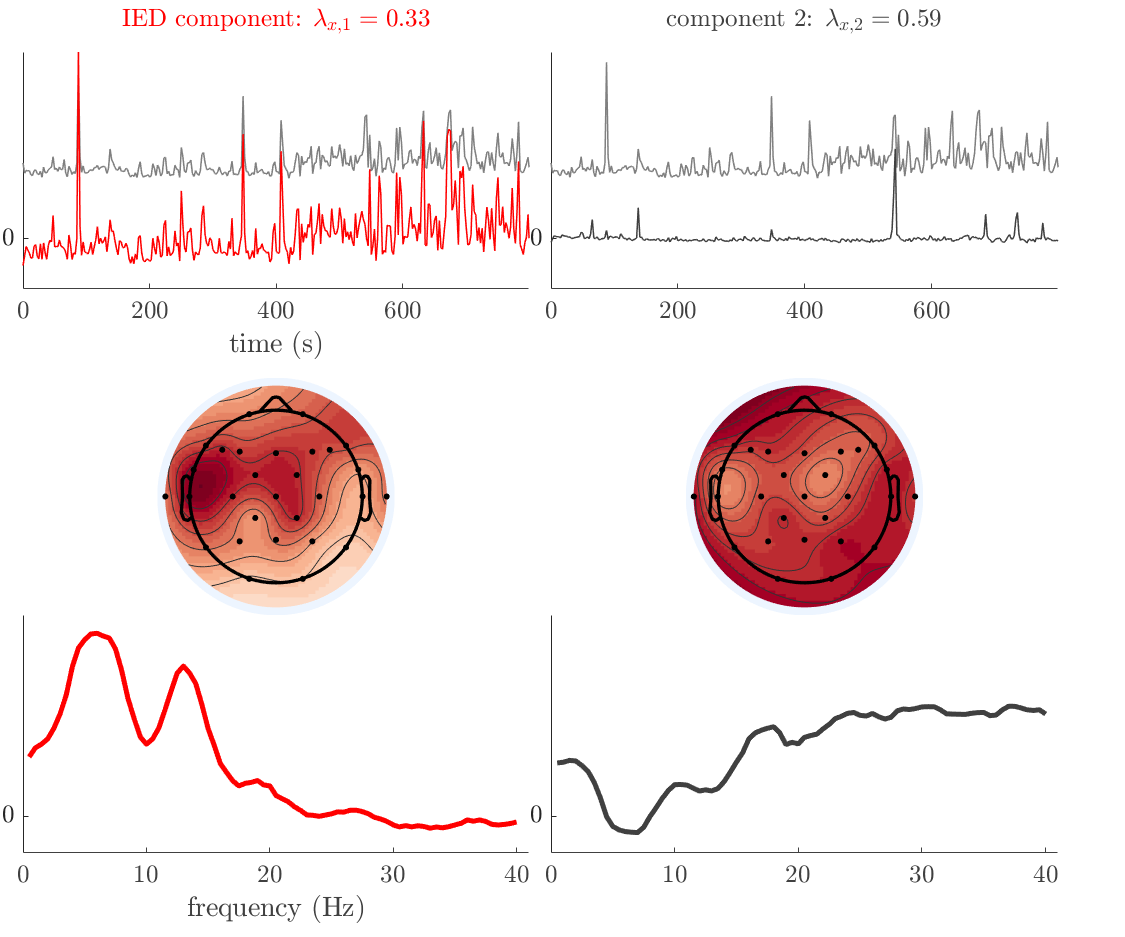

Patient 9

We analyze the solution with sources, and show the results in Figure 15 and 16. In this patient, there is only a moderate correlation of a component with the MWF reference time course. This component’s topography (left occipital) agrees with the clinical description, however. The HRF extremity (and not the entropy) is high in a small part of the IOZ. Both the significant IED activation and deactivation allow correct localization as well. The second source seemingly captured high-frequency oscillatory activity in the sensorimotor network, similar to the previous patient.